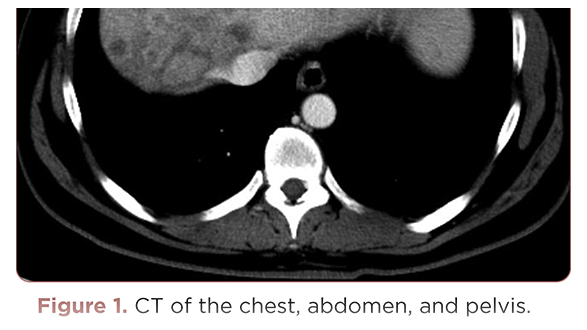

Management of Gastric Outlet Obstruction in a Patient With Gastric Cancer

Irene Thomas Thayil, PA-C

January 22, 2020